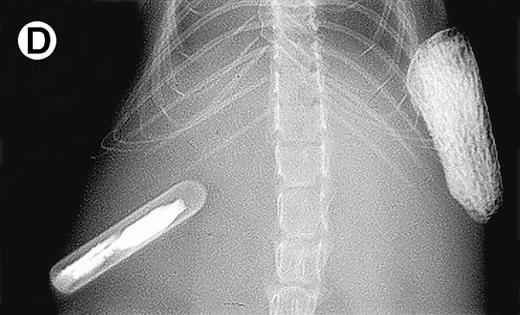

Growth of myeloma blood cells from patient no. 10 in SCID-hu host. SCID-hu host was inoculated with blood cells (containing 0.1% plasma cells) and with PC-depleted blood cells. (A) Human Ig levels. (•) Blood cells; (○) PC-depleted blood cells; (▪) host inoculated with bone marrow cells containing 11% myeloma plasma cells. (B) Flow cytometry dot plot of CD38CD45 profile of the blood cells. The sort window excluding CD45− and CD45+plasma cells is shown. (C and D) X-radiograms of host injected with blood cells (C) and with PC-depleted blood cells (D). Note severe decalcification of myelomatous human bone in (C).